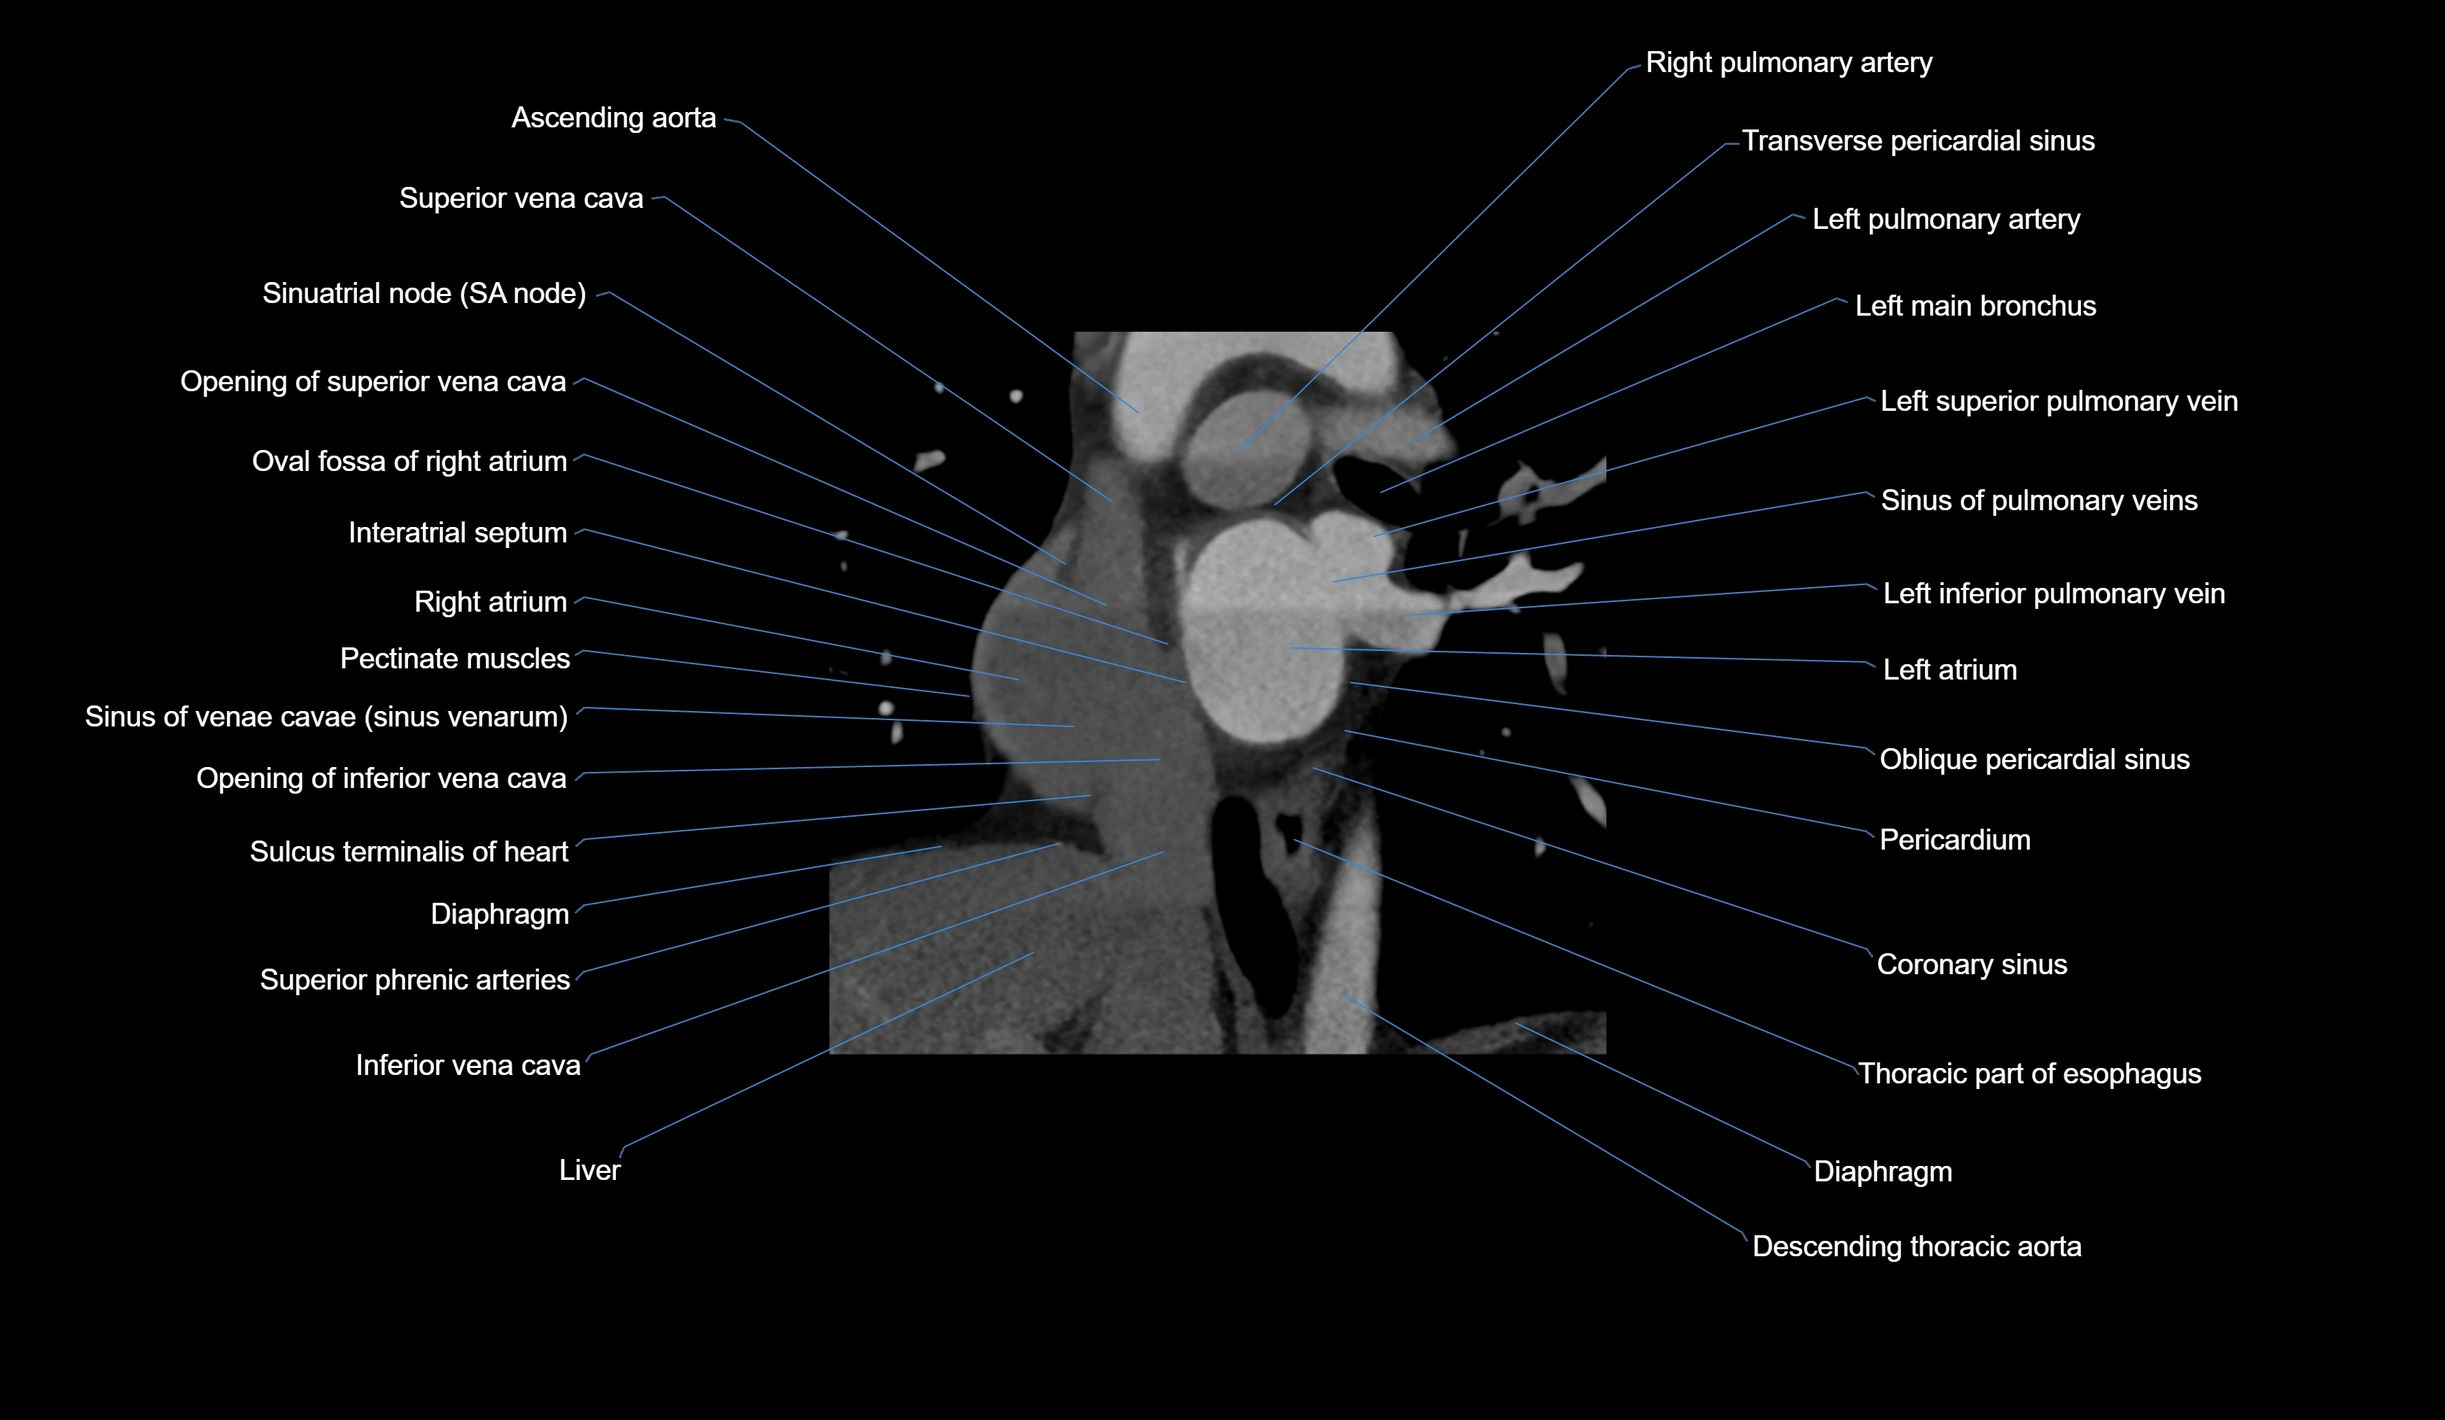

- Ascending aorta

- Superior vena cava

- Sinoatrial node (SA node)

- Opening of superior vena cava

- Oval fossa of right atrium

- Interatrial septum

- Right atrium

- Pectinate muscles

- Sinus of venae cavae (sinus venarum)

- Opening of inferior vena cava

- Sulcus terminalis of heart

- Diaphragm

- Right pulmonary artery

- Transverse pericardial sinus

- Left pulmonary artery

- Left main bronchus

- Left superior pulmonary vein

- Oblique pericardial sinus

- Left inferior pulmonary vein

- Left atrium

- Pericardium

- Coronary sinus

- Thoracic duct

- Descending thoracic aorta

- Inferior vena cava